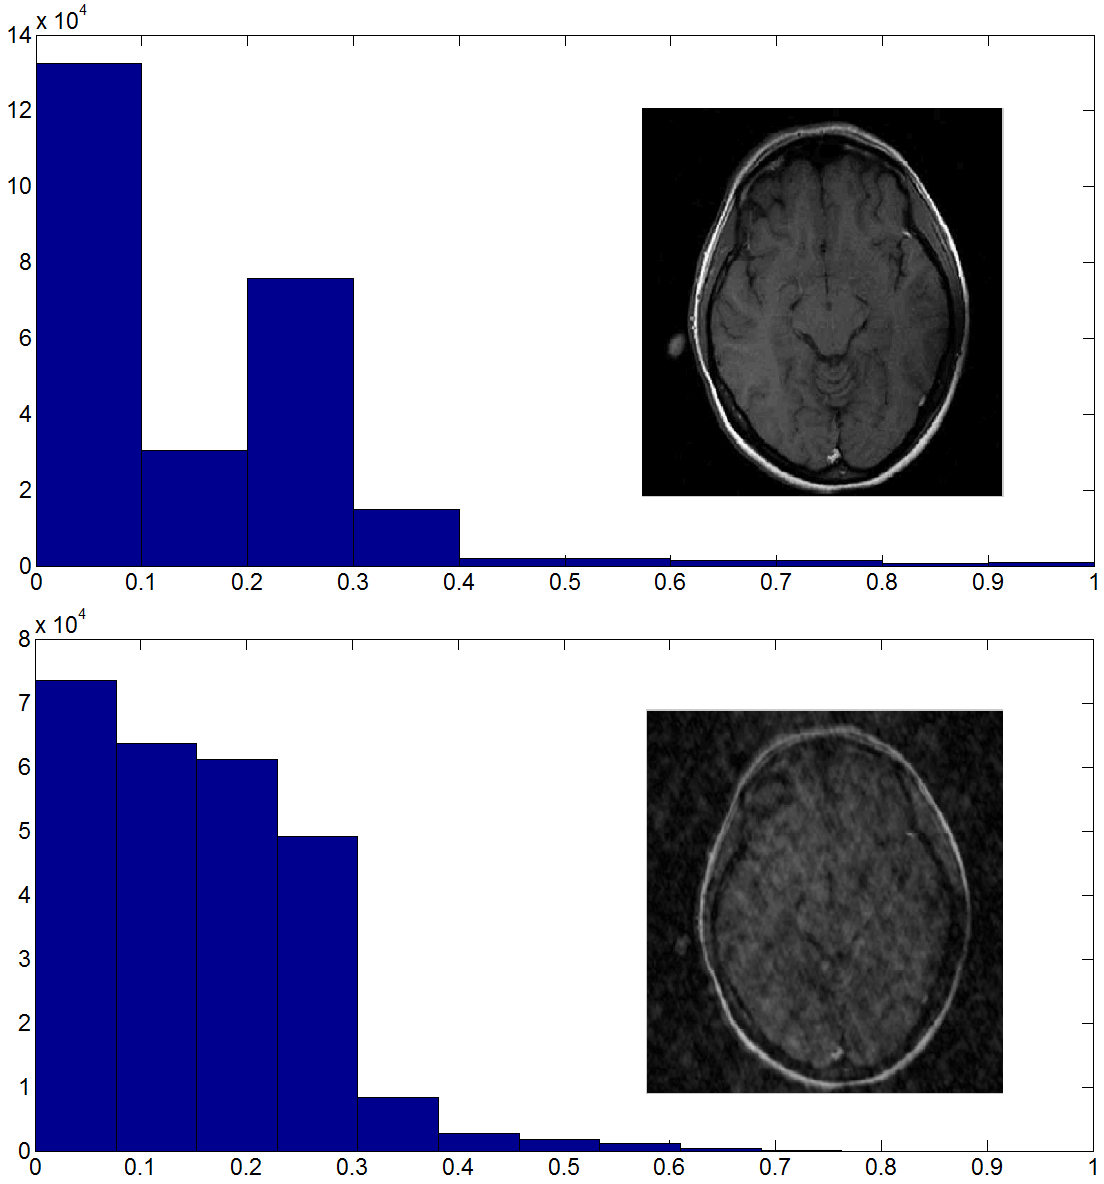

In this paper, we propose a simple yet fast and efficient algorithm for the reconstruction of MRI images. The idea is based on the evidence that MR images are sparser than their zero-filled reconstructed ones, i.e., the ones obtained as the inverse Fourier transform of the available Fourier samples by replacing the unknown samples with zeroes. This is illustrated in Fig. 1. In this figure, the histograms of one typical MR image and that of its zero-filled reconstruction are shown. As can be seen, the original image is sparser than its zero-filled reconstruction. This motivates us to formulate the image reconstruction problem as looking for the sparsest possible image conforming with the available Fourier samples. We solve it using the well-known Alternating Direction Method of Multipliers (ADMM) method. We work with the whole image instead of small overlapping blocks as in [11]. Our experimental simulations indicate improvements in both running time and quality of the reconstructed images, as compared to [11].

Consider an image . There are only a subset of its Fourier samples indexed in where with usually being much smaller than the whole samples, i.e., . The objective is to reconstruct the original image from its incomplete Fourier samples in . Hence, we exploit the evidence which was discussed in previous section and illustrated in Fig. 1. To measure the sparsity, we use the norm , which is defined as the sum of the absolute values of the entries in .